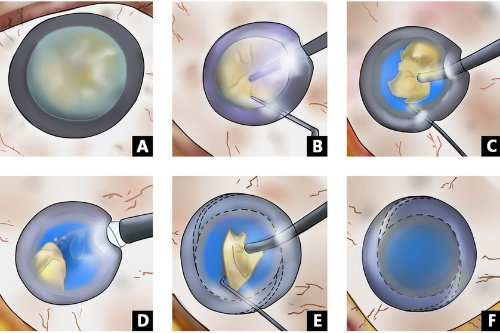

白内障专科:准屈光性手术

邵杰医师在白内障超声乳化联合功能性人工晶体植入方面经验充足,能够根据患者用眼需求定制散光矫正型、三焦点等个性化晶体,术后脱镜率高达92%。李凌副高医师则擅长糖尿病视网膜病变合并复杂白内障的联合手术,术后视力达标率优异。

特色技术:医院开展的微切口超声乳化手术,切口仅1.8mm,术后改善比较快,第二天即可获得良好视力。